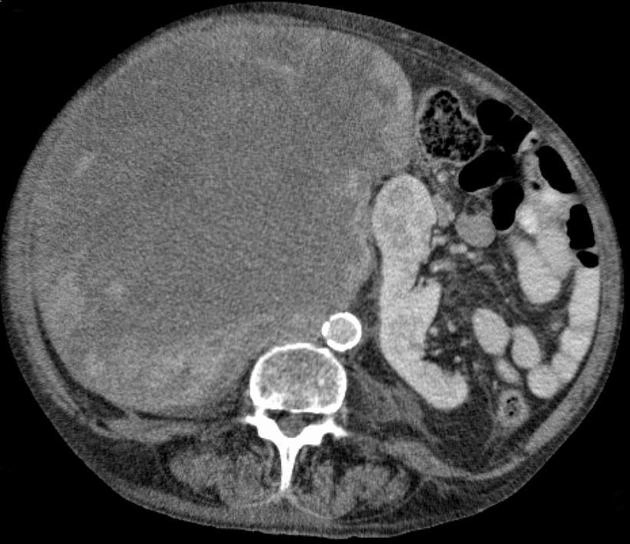

Sarcoma mỡ sau phúc mạc (Retroperitoneal liposarcoma)

16/03/2026